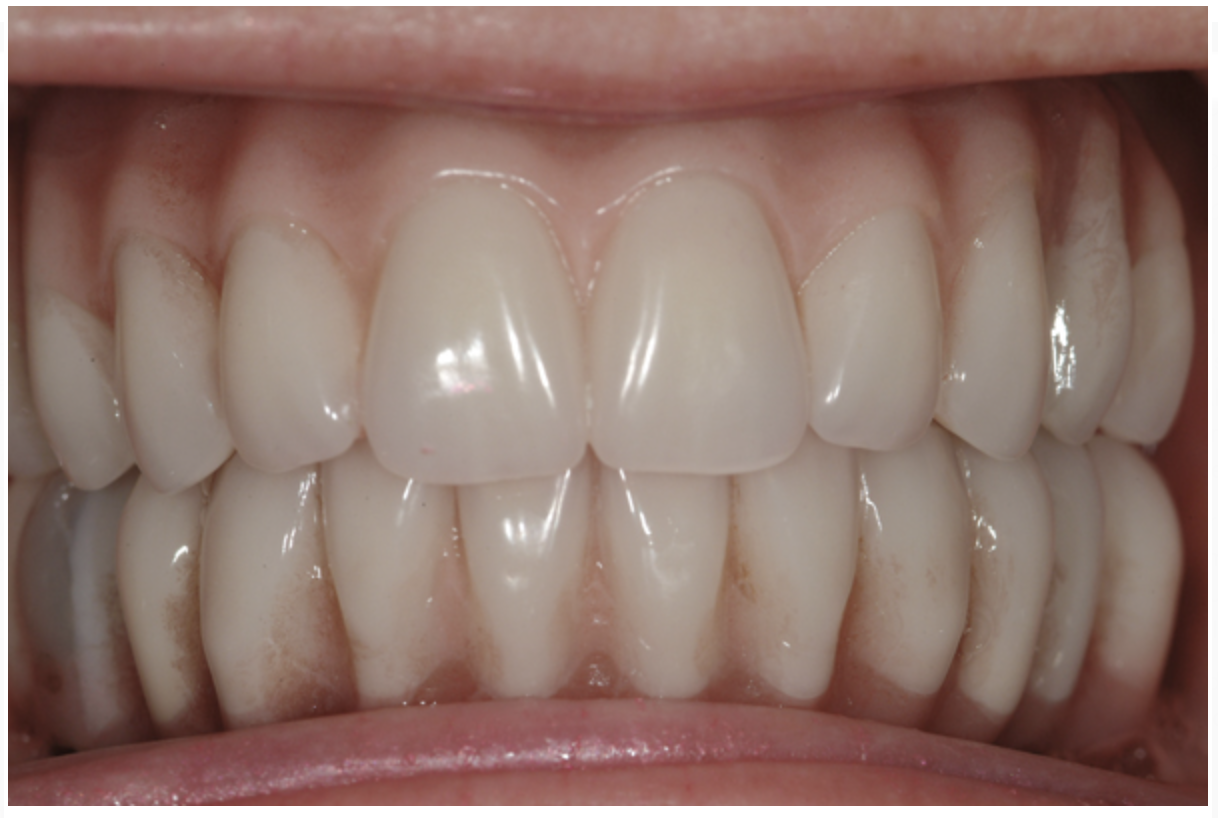

Dental rehabilitation with the All-on-4 treatment concept is often a life-changing event for edentulous and terminal dentition patients that results in unprecedented quality of life improvements (Figure 17 through Figure 20).

Fig 19. Patient smile shown 3 years post-treatment.

Figure 19

Fig 20. Patient intraoral condition 3 years following delivery of maxillary and mandibular All-on-4 definitive prosthesis.

Figure 20